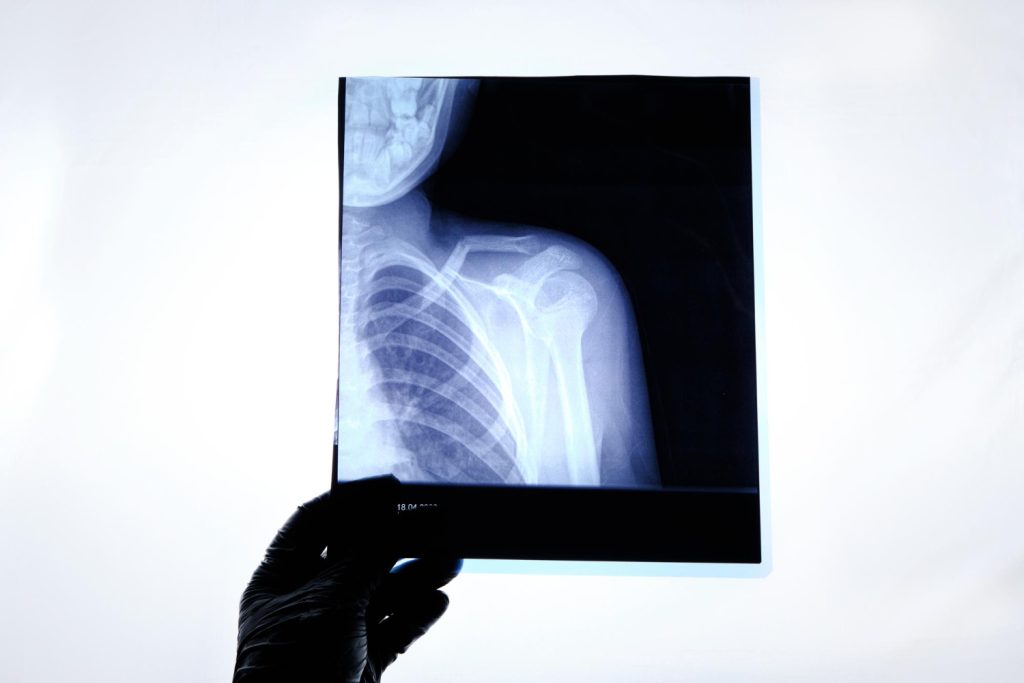

X-Ray Imaging

- X-ray imaging is commonly used to view bones and certain internal structures. It helps providers identify injuries, infections, and other medical conditions.

- X-rays may be used to evaluate:

- Bone fractures or injuries

- Joint problems